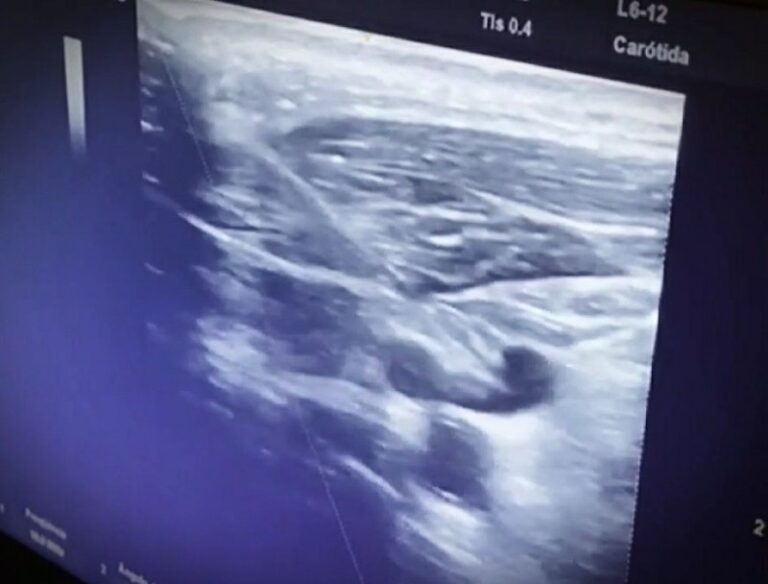

O Cateter Venoso Central precisa ser inserido em um vaso venoso calibroso, profundo. Quando indicado, é necessária escolha cautelosa do local de punção e precisão no decorrer da Técnica de Seldinger.